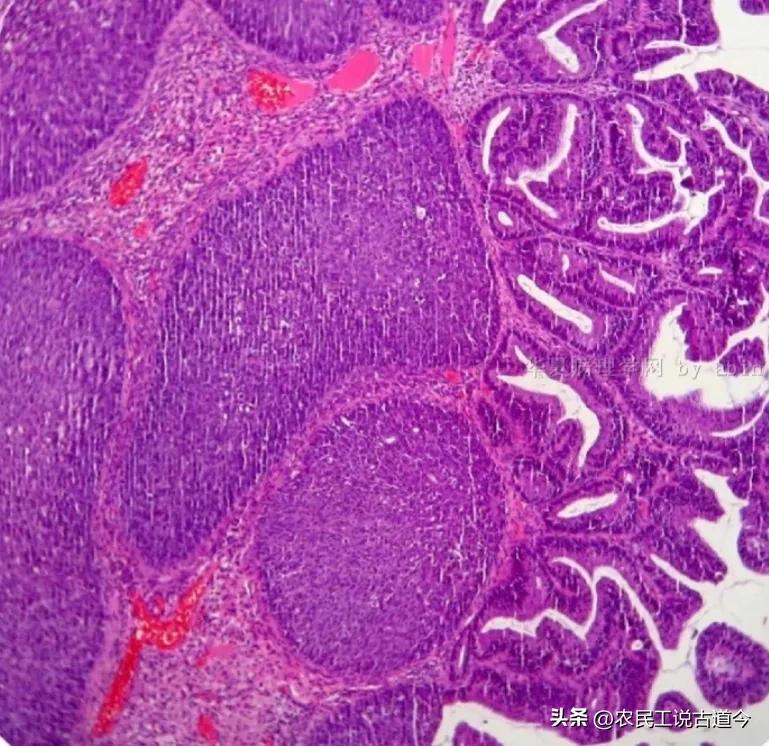

子宫颈高级别鳞状上皮内病变(HE染色)

然后是癌前病变。目前,子宫颈的癌前病变主要指高级别鳞状上皮内病变(即原来的CINⅡ、CINⅢ级和鳞状上皮原位癌)和低级别鳞状上皮内病变(即原来的CINⅠ级)。在组织学上,这些病变都没有突破鳞状上皮的基底膜,CINⅠ异型鳞状细胞通常位于鳞状上皮的下1/3;CINⅡ异型鳞状细胞超出鳞状上皮的下1/3、但位于2/3以内;异型鳞状细胞超过2/3则为CINⅢ级。以前,鳞状上皮全层见异型鳞状细胞、但未突破基底膜会被判读为鳞状上皮原位癌。但现在一般都归入高级别鳞状上皮内病变之中,不再单独报鳞状细胞原位癌了。还有就是一些单纯以“挖空细胞”为表现,没有出现细胞极性异常、鳞状细胞无明显异型性的情况,也被归入了低级别鳞状上皮内病变之中。